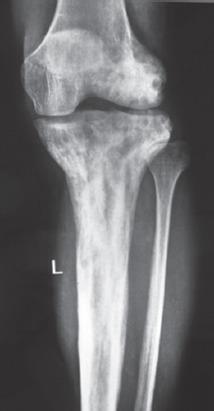

一名 40 岁男性因背痛就诊,经评估诊断为多骨型 PDB。他接受了静脉注射双膦酸盐、钙剂和维生素 D 补充剂治疗。在无症状的 3 年后,他出现了累及髂骨和骶骨的臀肌肿块,活检确诊为 GCT。尝试了系列血管栓塞术,但肿块仍进展,因此进行了手术,切除并刮除病变。2 年后他出现局部复发,伴有大量软组织成分。开始使用地诺单抗(一种 RANKL 抑制剂),目的是降低病变分期。患者在 6 次给药后显示出良好反应,软组织肿块缩小,随后接受了部分 T-1 型内部半骨盆切除术和骶骨刮除术。目前,患者在 15 个月的随访中无症状。